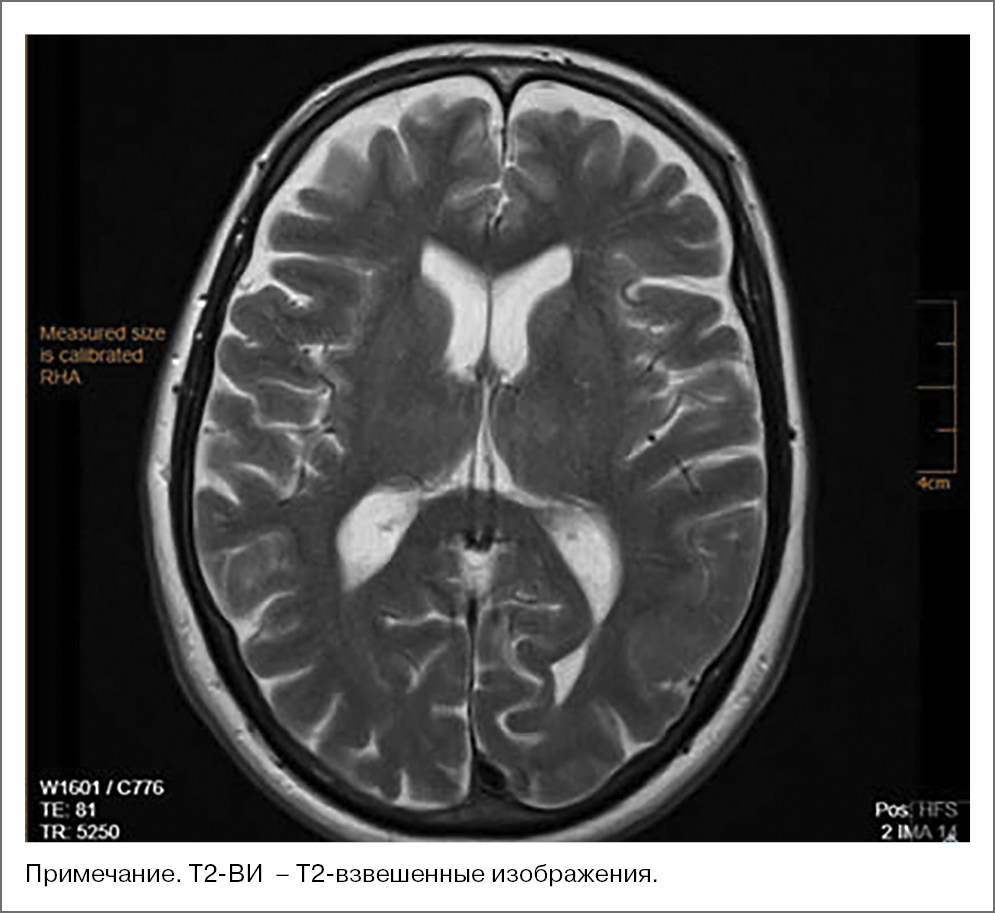

В динамике проведена МРТ ГМ, которая визуализировала в медиальных отделах таламуса с обеих сторон симметричные кистозно-глиозные изменения размером до 1,0×0,8 см, в кортикальных отделах правого полушария мозжечка мелкие глиозные изменения размерами 0,6×0,4 см (рис. 4).

Рис. 4. Пациентка С., 73 года. МРТ-исследование ГМ 04.03.2021: аксиальные МР-сканы последовательности Т2-ВИ, симметричный гиперинтенсивный МР-сигнал от правого и левого таламуса.